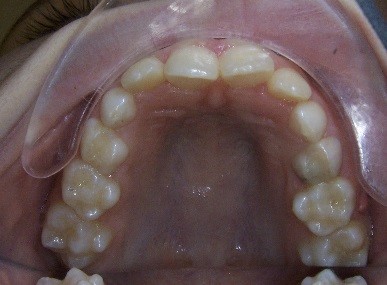

Key #2: An expander during the early mixed dentition allows the primary teeth to anchor the expansion appliance. This has significant benefits for permanent dentition that eliminate potential adverse effects, including dehiscence of the buccal bone, gingival recession, and root resorption. Expansion appliances use the strength of the roots and surrounding bone of the teeth to which they are attached. Consequently, those teeth and supporting bone carry the lateral pressure of the expansion as the suture opens. When primary teeth support the expander, the succedaneous bicuspids and canines do not bear any expansion pressure. The newly erupting teeth only benefit from the additional space development the expander has created. The acrylic bonded expander is easily constructed to adapt exclusively to the primary dentition, and has the added benefit of spreading the attachment over several teeth on each side. A banded hyrax appliance can be attached to the second primary molars and canines, or the permanent first and primary first molar. Studies have reported that using a Haas expansion appliance attached to the second primary molars and primary canines is successful and stable.